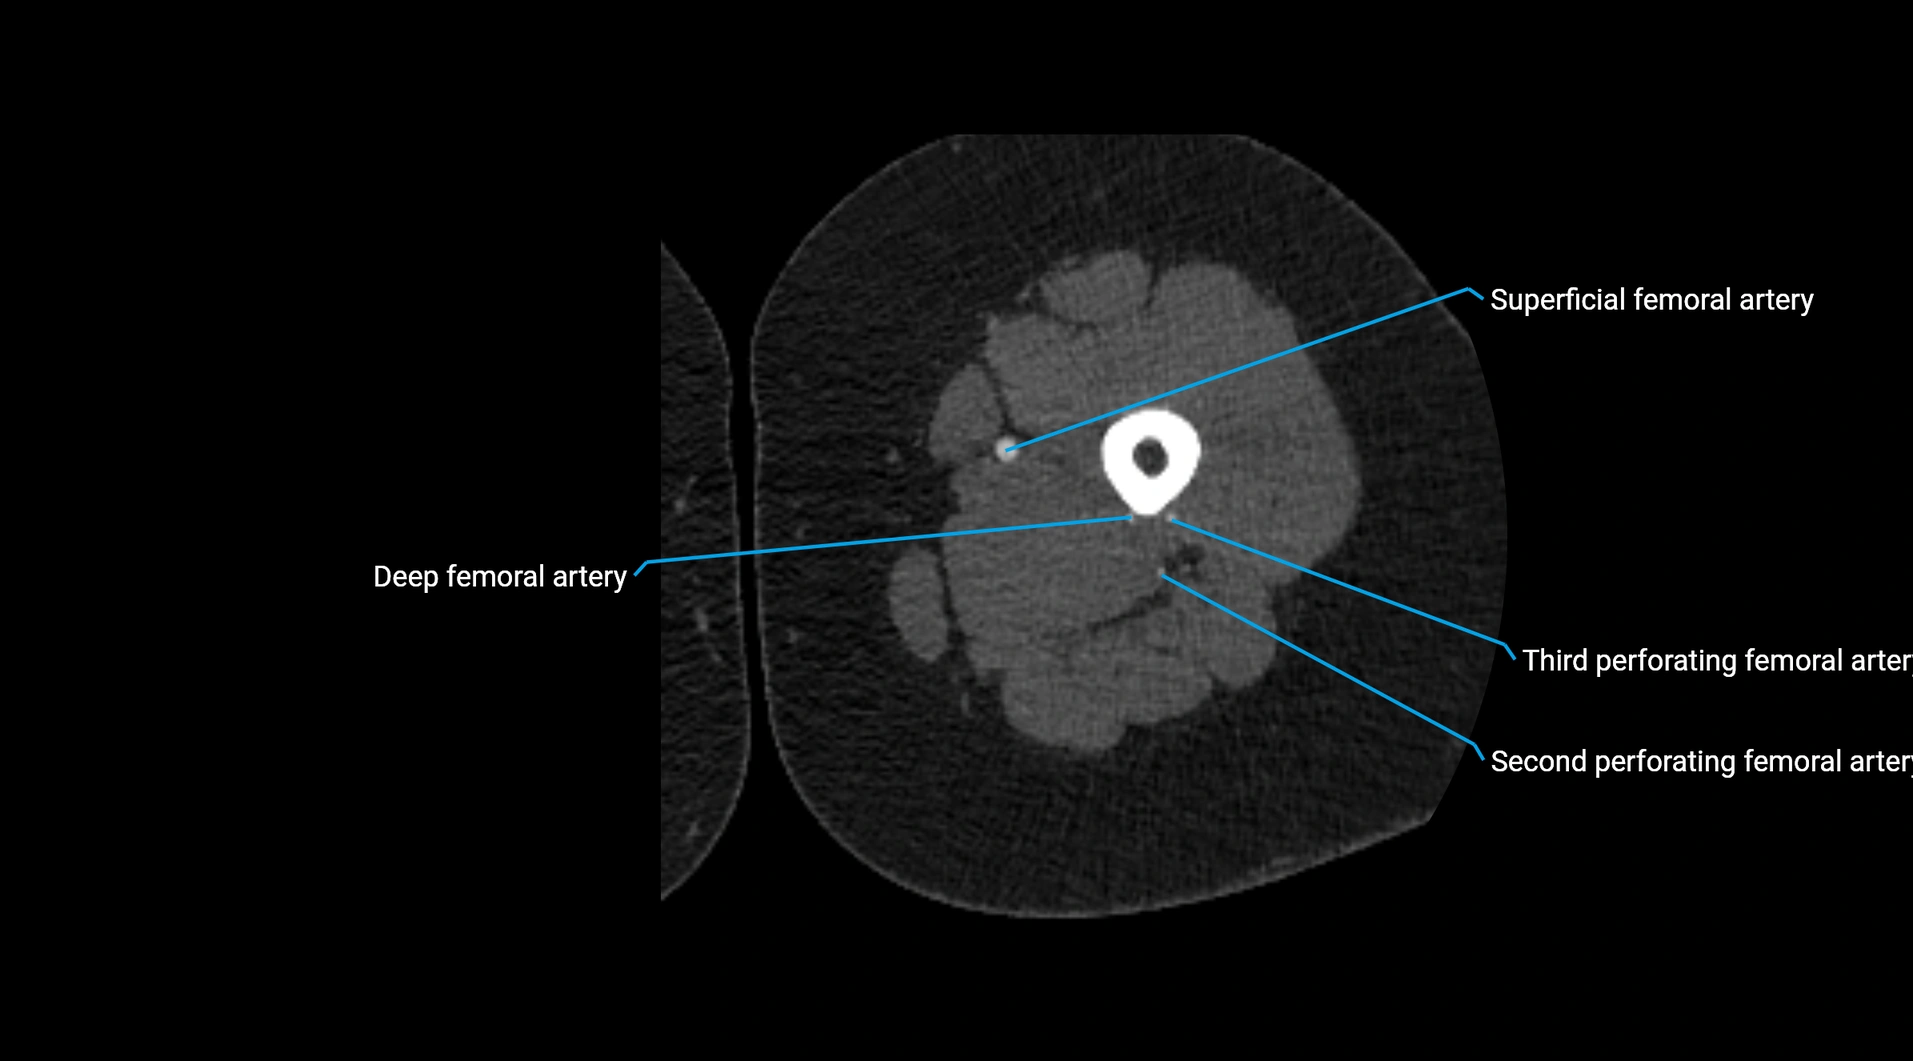

Contrast-enhanced CT (CTA):

• Gold standard for abdominal aortic imaging

• Provides excellent detail of lumen, wall, aneurysm, thrombus, and branch vessels

• Multiplanar and 3D reconstructions help in aneurysm measurement, stent graft planning, and dissection evaluation

• Detects acute rupture, traumatic injury, or occlusion with high sensitivity